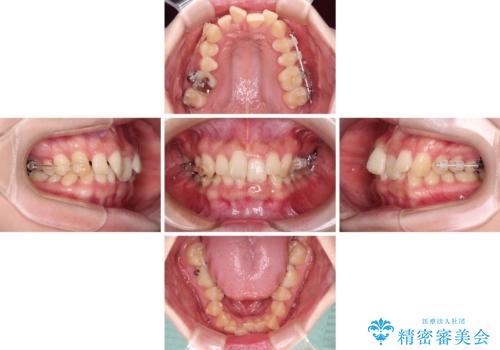

カリエールディスタライザーやワイヤー矯正を併用したことで、確実かつ短期間で治療を終えることができました。